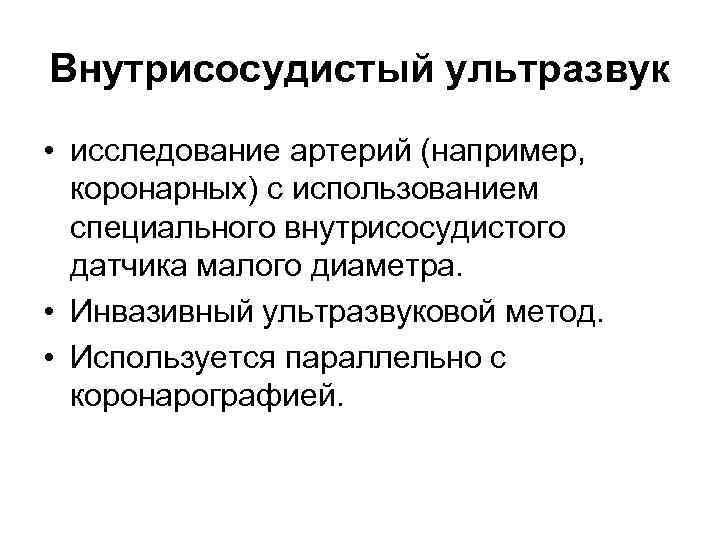

Внутрисосудистый ультразвук • исследование артерий (например, коронарных) с использованием специального внутрисосудистого датчика малого диаметра. • Инвазивный ультразвуковой метод. • Используется параллельно с коронарографией.

Внутрисосудистый ультразвук • исследование артерий (например, коронарных) с использованием специального внутрисосудистого датчика малого диаметра. • Инвазивный ультразвуковой метод. • Используется параллельно с коронарографией.